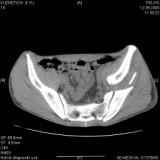

Повреждение вертлужной впадины 2,5 мес. |

Уважаемые коллеги! Хотелось бы услышать совет по тактике лечения представлленого больного.Поступил после лечения в одном изотделений области. Травма 2,5 месяца назад. После выведенияиз шока был произведен остеосинтез перелома бедра, предплечья, до перевода к нам проводилосьвытяжение по оси шейки бедра за стержень, введенный в большой вертел. На сегодня деформацияригидна, клинически мобильности не определяется. Заранее признателен. P.S. Данный вид травм не включен в перечень "высокотехнологичных операций", направить длялечения по квотам Минздрава очень сложно.

Это обзорные и косые снимки

Привет, Леонид. Оскольчатый высокий двухколонный перелом в такие сроки трогать не надо, т.к. это про такие переломы сказано: "кто с ножом на Ж. пойдет тот в ней и останется...".

Тяжелый случай... Поздняя реконструкция такого перелома технически сложное дело, вероятность осложнений,неуд.результатов выше(на PubMed article Johnson, Mast, Matta, Letournell results of acetabular reconstruction 20-120 days after injury).

Принимая во внимание обширность реконструкции, вероятность осложнений( остеоартроз, аваскулярный некроз), которые в любом случае должны будут решаться артропластикой сустава, пожалуй, я бы не стал оперировать сейчас: складывать мозаику многооскольчатого перелома, мобилизуя фактически сросшиеяся воедино фрагменты - дело травматичное с сомнительным результатом.

Думаю, что стоит подождать полной консолидации переломов и месяца через 3-4 при условии неудовлетворительной функции сустава артропластика.

Если заболит после начала нагрузки в 4-6 месяцев - эндопротез.